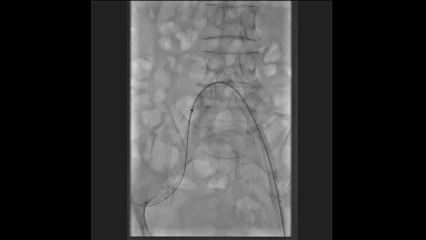

造影确认病变

造影显示髂外动脉起始至股总动脉远端完全闭塞,股总动脉见大斑块。

髂动脉处理

使用Admiral球囊扩张后,植入12cm长Everflex支架覆盖病变,形态良好。